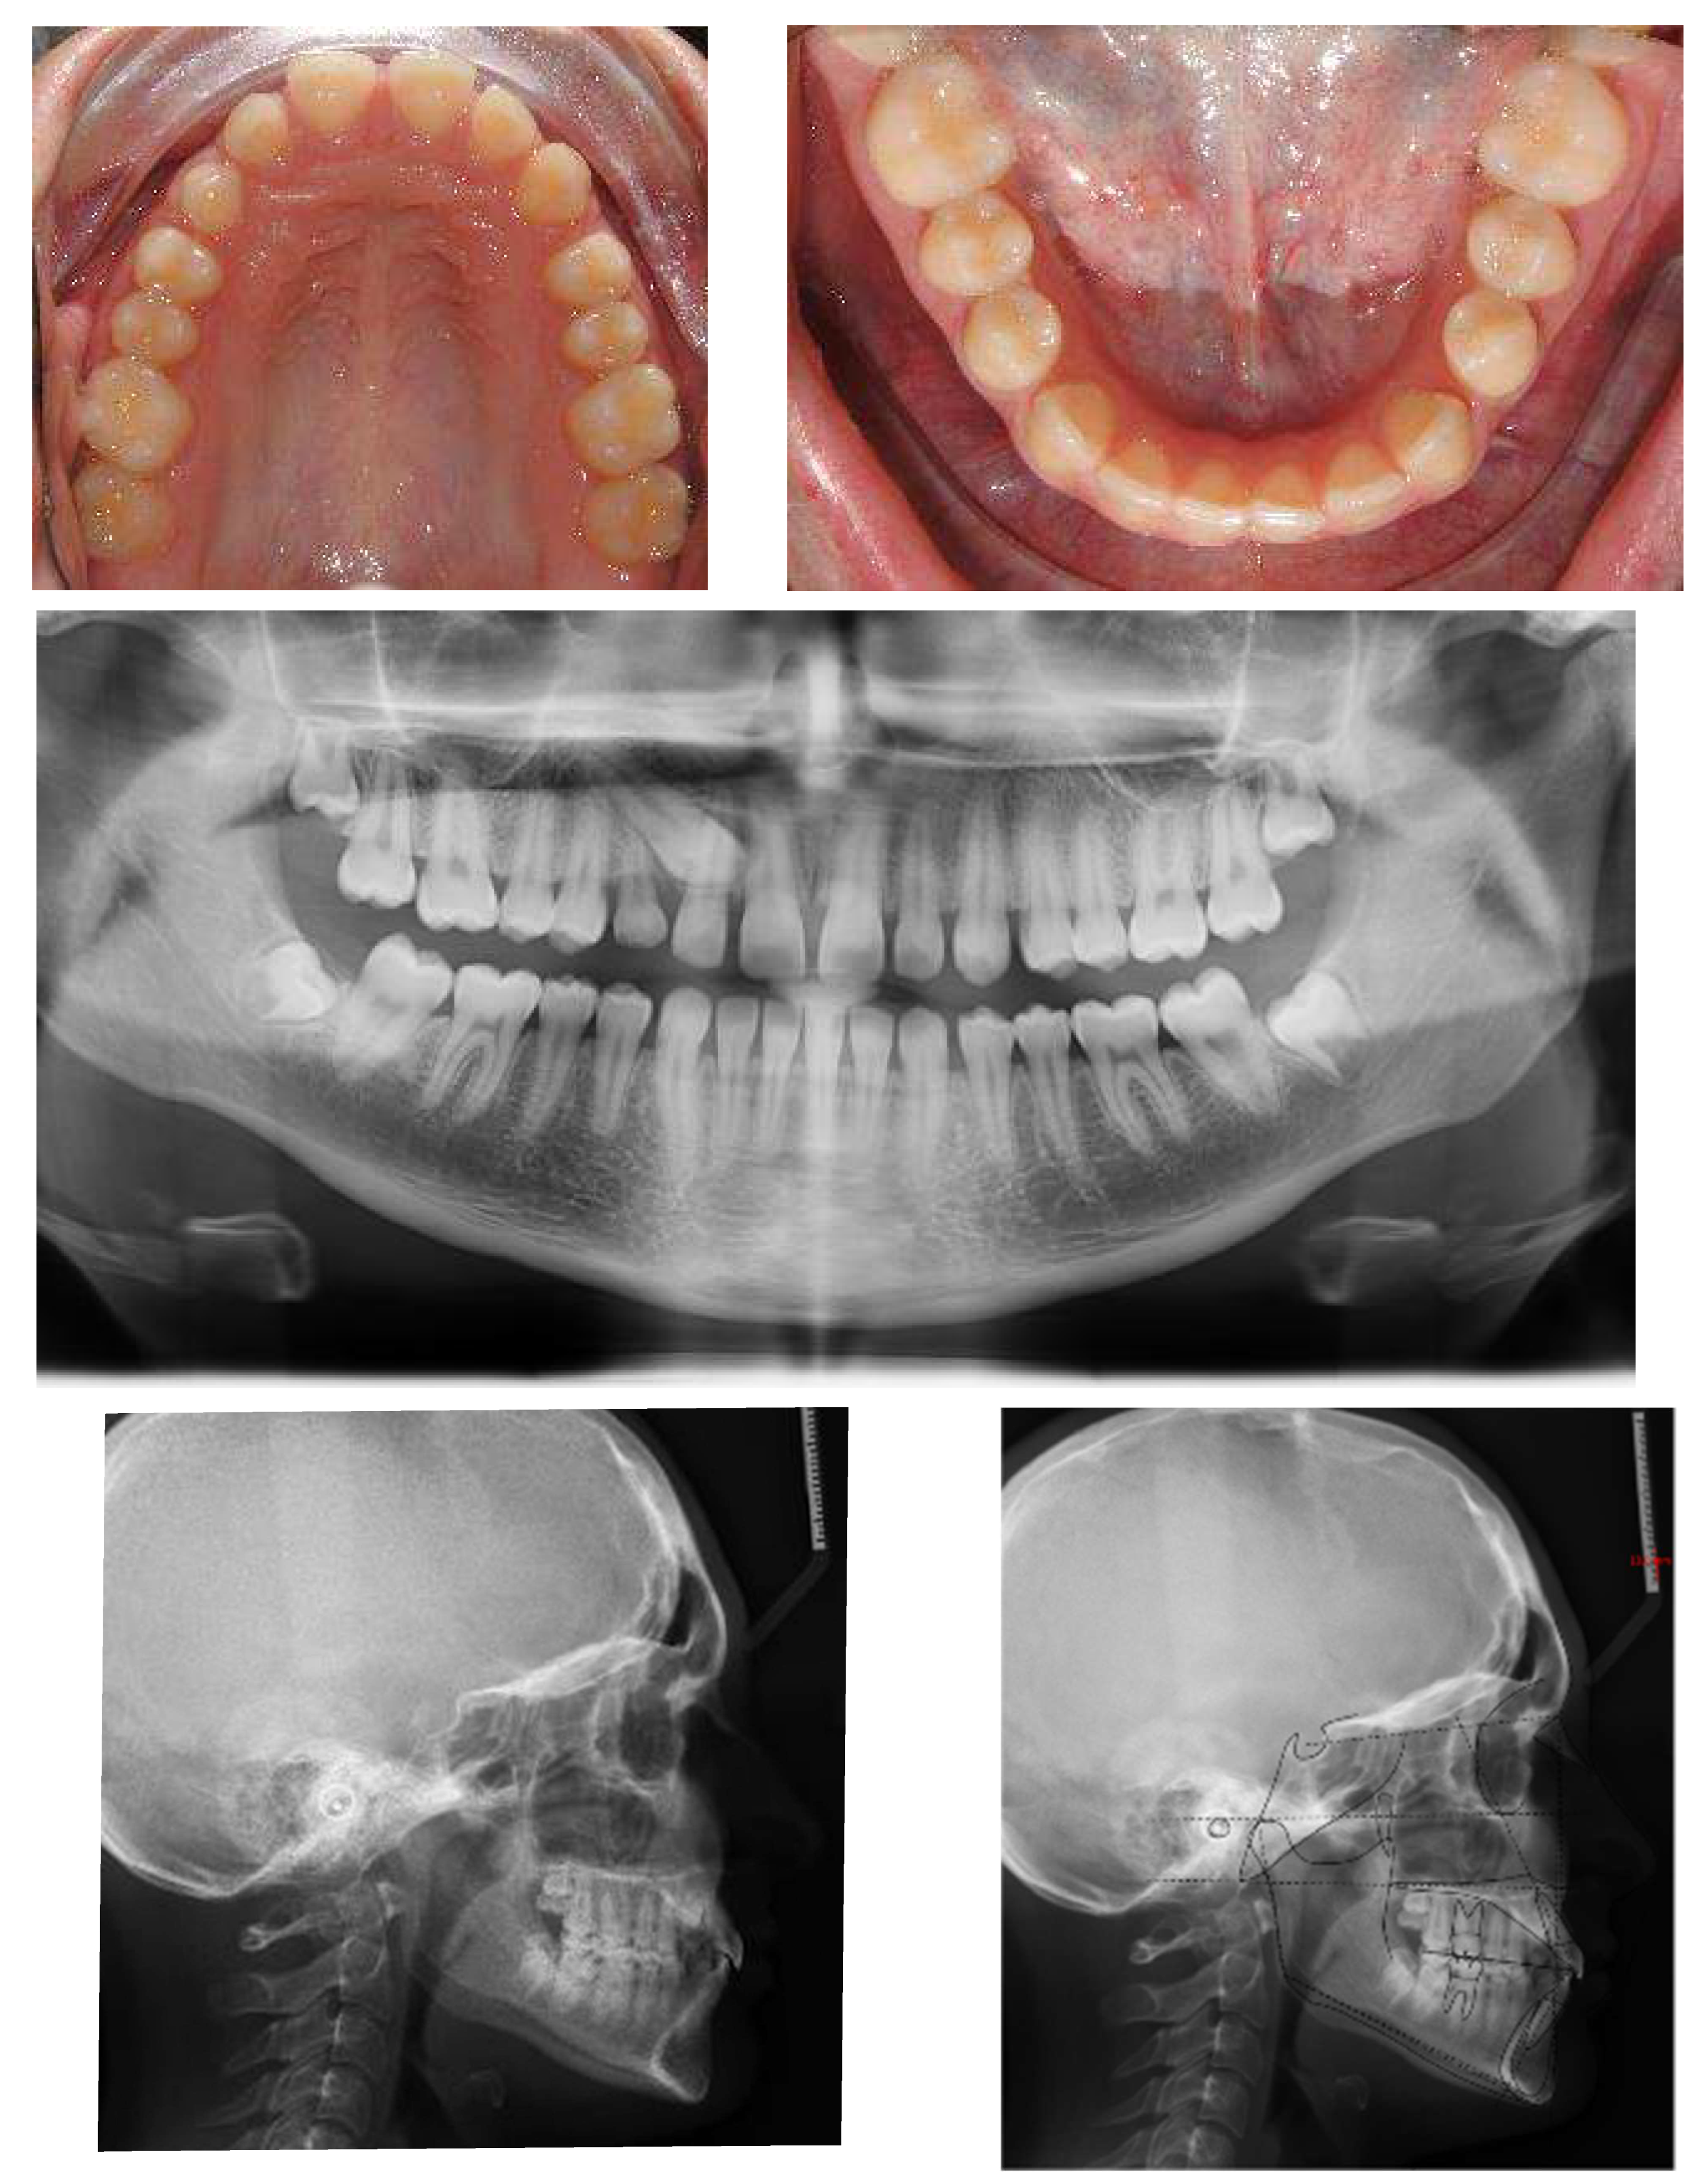

An 18-year-old female patient was referred, complaining of unpleasant smile. She presented good general health and no systemic or congenital diseases. From a frontal view, the patient presented a well-proportioned three-thirds of her face and no evidence of asymmetry. From the lateral view, the profile appeared convex with well-represented nasolabial angle, labiomental sulcus, and lip competence. Intraorally, the patient showed a Class II malocclusion with the molar Class I relationship, edge to edge canine relationship on both sides, increased overjet, overbite, and the retention of the 63. Panoramic, lateral headfilm, and dental cast records were taken (Figure 11).

Figure 11.

An 18-year-old female with dentoskeletal Class II with impacted upper left canine before treatment.

The initial cephalometric analysis showed a skeletal Class I relationship (ANB, +2.6°) and mesodivergent pattern with the proclination of the upper (I/ANS-PNS 118.8°) and lower (i/GoGn:102.2°) incisors. All the radiographic findings, the age of the patient, the prolonged deciduous retention, and the risk of root resorption of the adjacent tooth, led clinicians to conclude that the permanent canine would not erupt properly without intervention (Table 2).

The position of the impacted canine showed an alpha angle of 58° and the Ericson and Kurol II sector classification. No clinical symptoms on articular examination were detected (Figure 12).

Figure 12.

Pre-treatment panoramic X-ray with the evaluation of alpha angle and sector according to the Ericson and Kurol classification.